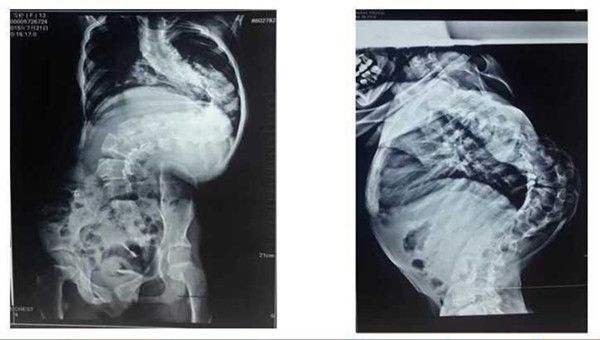

手术前后的X线片对比,矫正效果基本满意

手术前,学科带头人贺西京教授、李浩鹏主任邀请有丰富麻醉经验的李有才教授,以及主管医生,根据患儿全身状况,进行细致的病例讨论,制定周密的手术方案。于8月18日,由贺西京、李浩鹏教授亲自主刀,主管医生张纯、杨宝辉、蔡璇等配合,李有才教授负责麻醉,对患儿实施全麻下全脊柱截骨矫形术,术中在严密保护脊髓的前提下,将脊椎一节节打断、截骨,再重新排列、固定。因脊柱畸形严重,常规固定方式无法完成,只能凭经验探索进行,多次进行术中透视。如此大范围脊柱矫形,风险极大,术中稍有不慎,无论是术中操作,还是骨片,都有可能损伤血管造成大出血,危及生命。在完成椎体截骨时,脊髓也要完成近120度的变位,此时极易损伤神经,风险极大。神经损伤会造成患儿终身瘫痪,双下肢丧失运动、感觉功能,并出现大小便失禁等,因此要求术者一定要心细,操作要轻、准。手术全程在诱发电位严密监测下进行,及时反复监测神经传导速度,判定神经功能。在手术、麻醉及护理人员的紧密配合下,经过近10小时紧张、细致的手术,手术取得成功,矫形由患儿颈后部到腰下段的脊柱全段,缝针36针,术中输血1800毫升,术中矫正脊柱畸形角度约120度。术后患儿即可平卧,背部大驼背畸形显著改善,双下肢感觉、运动良好,自解小便,目前正在积极康复中。